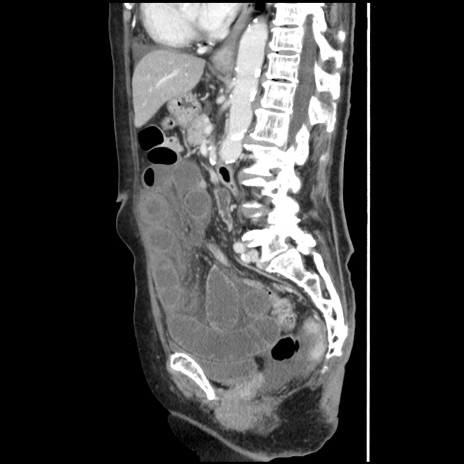

冠状断像

【症例】80歳代女性

【主訴】腹痛

【現病歴】8時間前から腹痛あり来院。

【既往歴】糖尿病、脂質異常症、子宮体癌にて子宮全摘術

【身体所見】意識清明・会話良好だが腹痛で苦悶様、全腹部にわたって反跳痛と圧痛あり

【データ】WBC 13600、CRP 0.14、LDH 224、CK 90